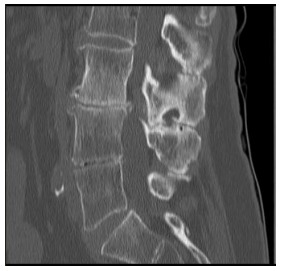

O corte tomográfico sagital da coluna lombar abaixo ilustra claramente alterações que possibilitam alguns diagnósticos, dentre os quais podemos citar: